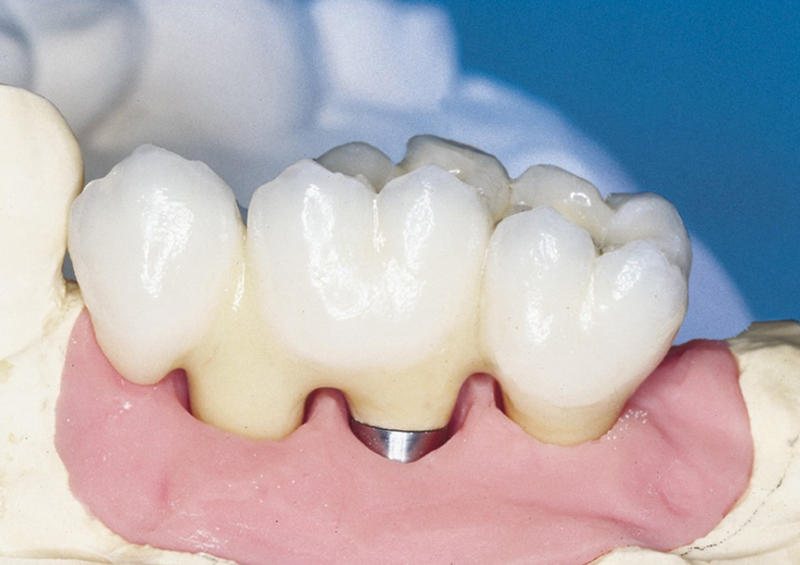

Protetické řešení může být pomocí můstku, který je kotvený na implantátech nebo pomocí jednotlivých korunek na implantátech.

V zásadě je možné do těchto můstků zařadit i přirozené zuby, zejména pokud je potřeba tyto zuby ošetřit proteticky

- korunkami. Korunky nebo můstky mohou být na implantáty nacementovány nebo přišroubovány.